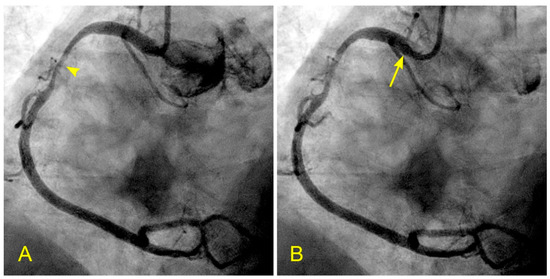

Figure 14.

(A,B) Recirculating flow due to blood converging from two branches in the retrograde direction. (A) Coronary angiogram of an elderly patient with a severe lesion proximal to the bifurcation of the distal right coronary artery (RCA) and the posterior descending artery (arrow). (B) The blood converges from a large main branch and one smaller side branch (The yellow arrows point to the retrograde direction of the blood flow). Because of differences in velocity, the flow at the inner curve recirculates and starts a slow atherosclerotic process [10].

Figure 15.

(A–F) Reverse flow in distal right coronary artery. This is a series of six sequential images separated by 6 milliseconds each (15 images per second). (A) The blood, in white, moves forward to the distal right coronary artery (RCA) (arrow) past the origin of the posterior descending artery (PDA) (arrowhead). (B) The blood (white) is now clearly distal to the origin of the PDA (arrow), while the contrast at the origin of the PDA stays stagnant and homogenously black (arrowhead). (C) Flow reversal. At the beginning of systole, at the distal RCA, the contrast reverses its direction and flows back past the origin of the PDA (arrow). (D) At the distal RCA, the blood (in white) pushes back the contrast (arrow) in the antegrade direction. The flow reversal is short-lived. (E,F) At the distal RCA, the blood, in white, moves forward as usual (arrow). If the reversed flow had been strong and lasted longer, more damage could have been inflicted on the endothelium and could have triggered the atherosclerotic cascade.